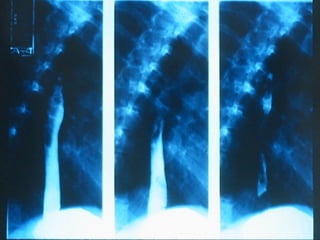

SEGD Puntos normales de estrechamiento del esófago A nivel cartílago cricoides Altura de botón aórtico Donde cruza el bronquio izquierdo El sitio donde pasa a través del diafragma

SEGD Puntos normalesde estrechamiento del esófago A nivel cartílago cricoides Altura de botón aórtico Donde cruza el bronquio izquierdo El sitio donde pasa a través del diafragma